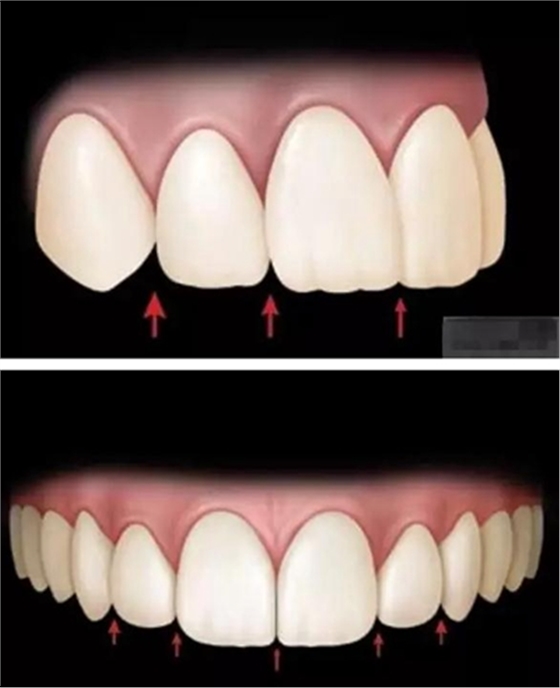

審美序列清單:

1、切牙的位置長(zhǎng)度

2.頜學(xué)

3.牙齒寬度

前牙的黃金分割比例

正面觀

側(cè)切牙約為中切牙的60%

尖牙約為側(cè)切牙的60%

4.牙齒比例

中切牙正常/理想的 寬/長(zhǎng)百分比約為75%—80%